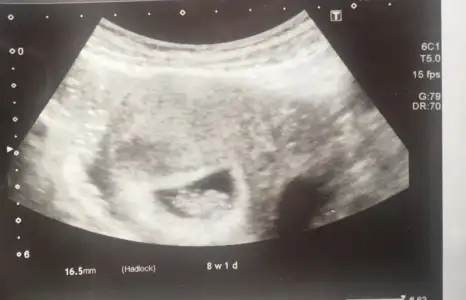

Ben koyayımburda 8+1 haftalıktık şimdi iseee 8+6 olmuşuz bile